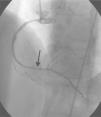

A 64-year-old white woman with a history of hypertension was admitted to hospital with new-onset chest pain consistent with angina. She had had multiple coronary angiograms (CA) four years previously for repeated episodes of typical chest pain and admissions. The CA showed non-obstructive coronary artery disease in the range of 40–50% in the left circumflex artery (LCx) which was confirmed to be non-obstructive by fractional flow reserve during the angiogram; no catheter-induced vasospasm occurred during the CA. Because of continued episodes of chest pain, she was taken off metoprolol and started on diltiazem 240mg once a day for possible vasospastic angina. She was then asymptomatic for the following four years, and also had a dobutamine stress echocardiogram, which was negative, about two months before the present admission for screening due to disease identified on her last CA. At this admission, she had new symmetrical anterolateral and inferior T inversion on the ECG consistent with ischemia; troponin levels were minimally elevated (0.3ng/ml). The patient had been seen by her primary care physician three days previously for a routine follow-up and was taken off diltiazem and started on nebivolol 10mg/day in addition to her medications of HCTZ 25mg and lisinopril 40mg/day, Lipitor 40mg, and enteric-coated aspirin 325mg/day for blood pressure (BP) control. In hospital she was started on nitro paste and intravenous (IV) heparin and her home medications continued. Because of continued chest pain in hospital and mildly elevated troponin I levels, she was scheduled for CA. She experienced chest pain at the beginning of the coronary angiogram, which initially revealed a 70% lesion and slow flow in the mid left anterior descending artery (LAD), a 90% lesion in the mid LCx and a 99% lesion in the ostium of the second obtuse marginal (OM2) (Figure 1, black arrow). The right coronary artery (RCA) had a distal 80–90% stenosis (Figure 2, black arrow). During preparation for percutaneous intervention in the LCx and OM2, intracoronary (IC) nitroglycerin was given for vessel sizing, after which there was resolution of the lesions in the LAD and decrease in the mid left LCx lesion to 50–60%, and resolution of the OM2 lesion, suggestive of significant reversible coronary artery spasm (Figures 3 and 4, white arrows). IC nitroglycerin was also administered in the RCA, in which lesion resolution was also seen. The coronary intervention was aborted, the patient's chest pain was resolved after IC nitroglycerin and she was started on IV nitroglycerin in the interim. Nebivolol was discontinued; diltiazem started in post-catheterization orders. She continued to have occasional episodes of chest pain for about 24hours after discontinuation of nebivolol. She was weaned from IV nitroglycerin the next day and started on oral isosorbide mononitrate. The following day the ECG changes resolved with no more episodes of chest pain; she was discharged home and was event-free in follow-up.